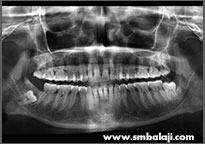

CASE IV

X-ray showing impacted upper right and left third molar teeth

Impacted teeth surgically removed